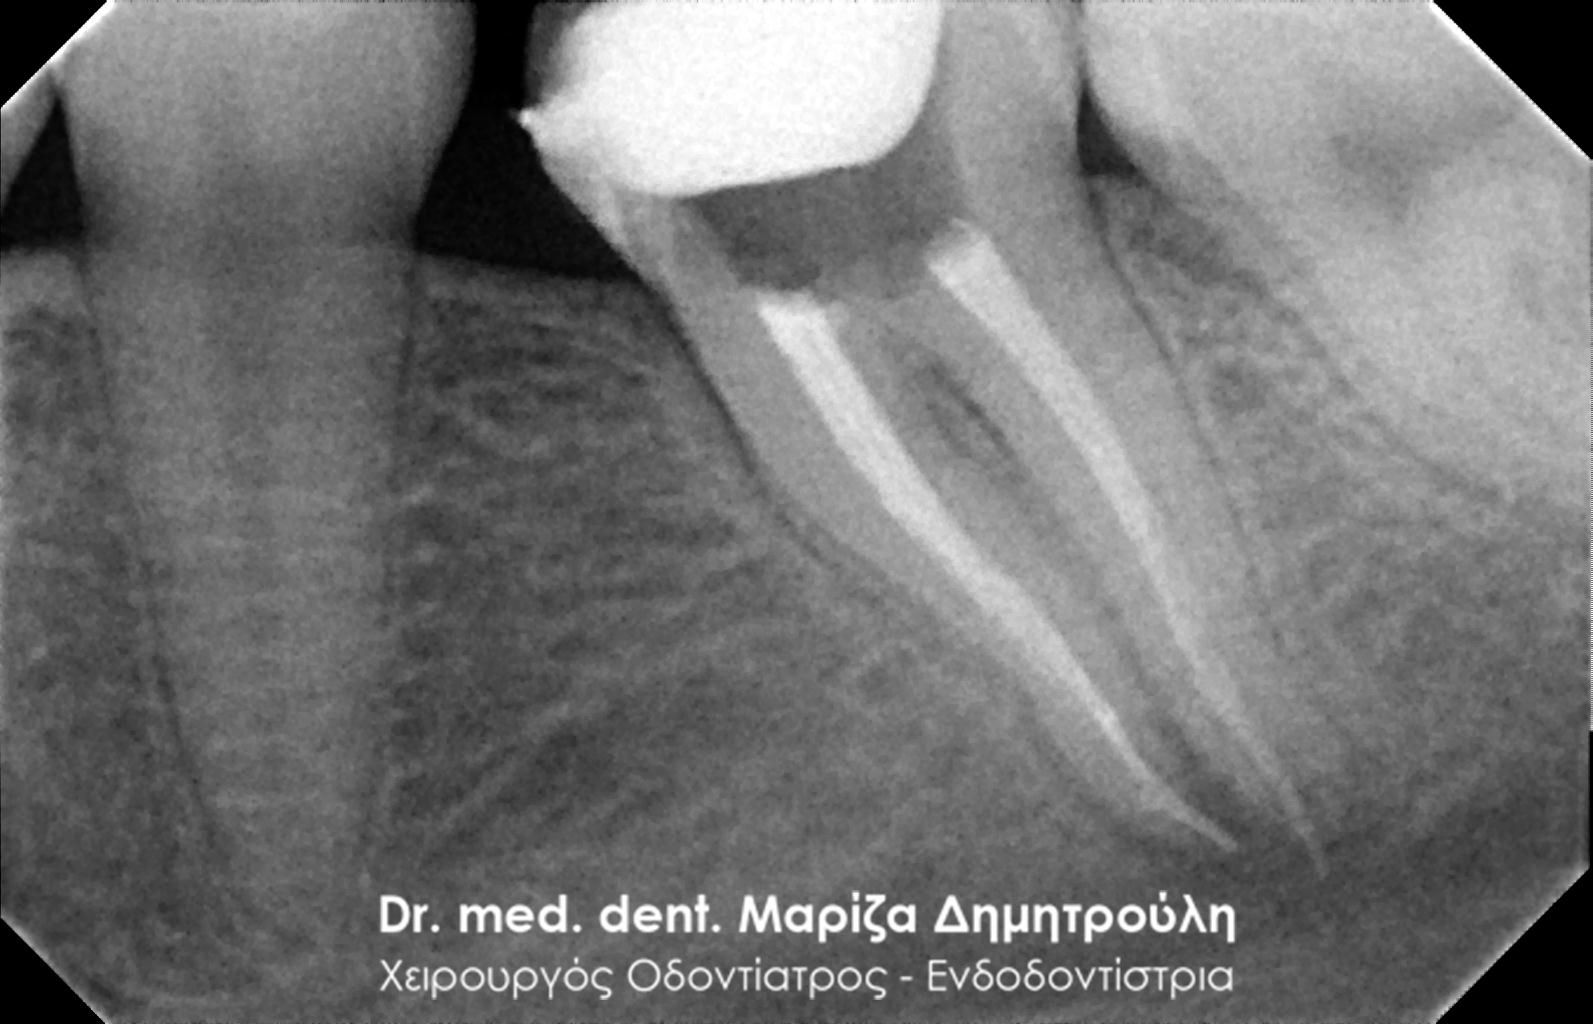

Root canal retreatment

Control of removing the old root canal filling

AFTER